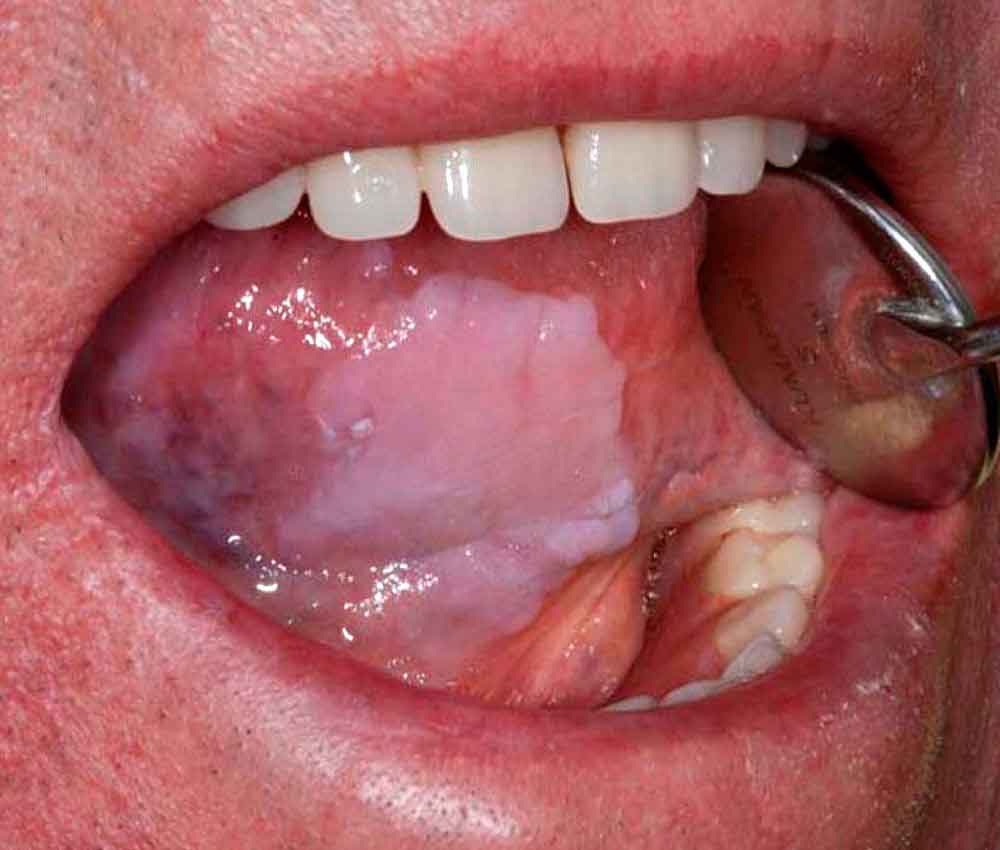

ORAL MEDICINE : A guide to common oral lesions

Diagnosing and treating dermatologic lesions of the mouth and gums is challenging for most clinicians because of the wide variety of disease processes that can present with similar appearing lesions and the fact that most clinicians receive inadequate training in mouth diseases.

This review will discuss the presentation and treatment of the most common oral lesions, including tumors, infections, autoimmune and connective tissues diseases, aphthous ulcers, and other miscellaneous oral lesions.